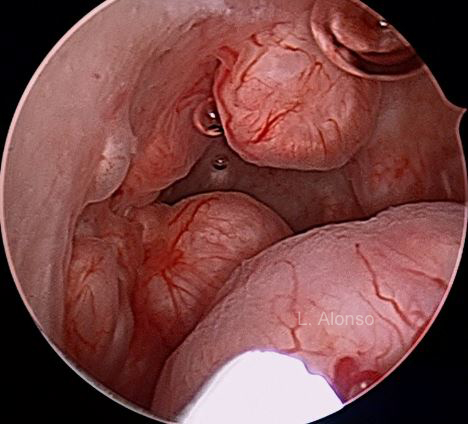

The most interesting biological activity that has been highlighted in the myoma pseudocapsule is that concerning the neoangiogenetic activity. In fact, myoma pseudocapsule is plentiful of collagen fibers, neurofibers and blood vessels (Figure 3), as a neurovascular bundle surrounding fibroid. Within the neurovascular bundle, some neoangiogenic factors were also studied. Angiogenetic factors identified in the pseudocapsule vessels are already widely involved in the physiology of the myometrium.